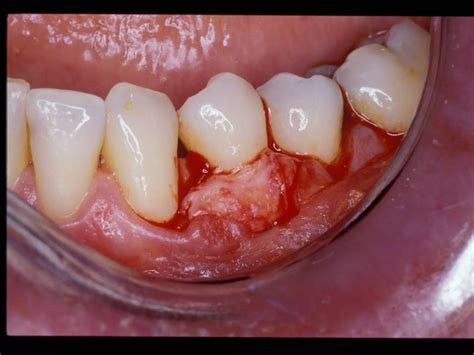

ROOT COVERAGE PROCEDURES | PPTX

Root Coverage Gallery | Gum Recession Treatment Guelph